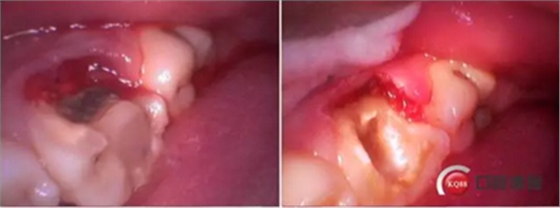

牙列完整,后牙中性關(guān)系,前牙開合,中線對齊。16合面大面積齲壞,內(nèi)褐色腐質(zhì),冷診無反應(yīng),叩痛(+-)。36合面樹脂充填,充填物在位,頰側(cè)冠折,折線位于齦緣下,冷診無反應(yīng),叩痛(+)。其他無殊。

診斷:36冠根折。

這是折線的位置,右是拔出的牙齒碎片。很明顯折裂波及遠中頰根。

先去了充填物,去腐,牙齦電切。根折根上段少量,沒有破壞根管結(jié)構(gòu)。選擇保留患牙。

牙齦切除后,根折面平整拋光,恢復(fù)頰側(cè)壁。

牙齦電刀切除,樹脂做頰側(cè)壁。